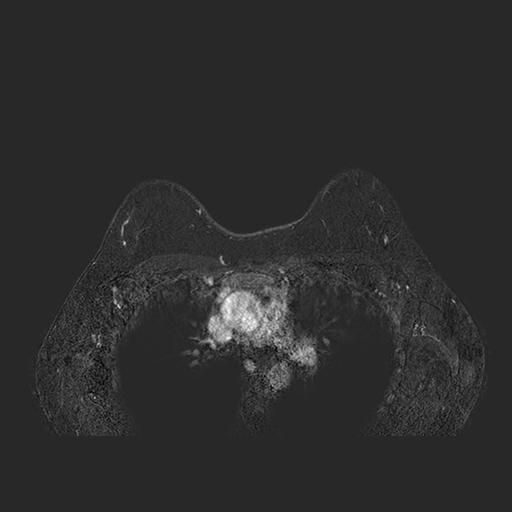

To close off this day, I also did a magnetic resonance imaging (MRI) exam with a contrast medium. The question to answer here was mainly: is my tumor a solitary lesion? or part of a bigger, scattered group? and how big is it? are my axillary lymph nodes healthy or not? This is the imaging modality for dense breast imaging: it’s also, unfortunately, very expensive.

The doctors panicked here a little bit, as the MRI showed weird inflammatory activities around my axillary zones: it turned out this was due to the double shots of vaccine I had 24 hours before (both for COVID and for the seasonal flu). Admittedly not a great timing, but I needed to help my immune system as fast as possible before starting chemotherapy. Yes, those up there are my boops as I breathe in and out on the machine. The exam was long, uncomfortable, and loud as hell.